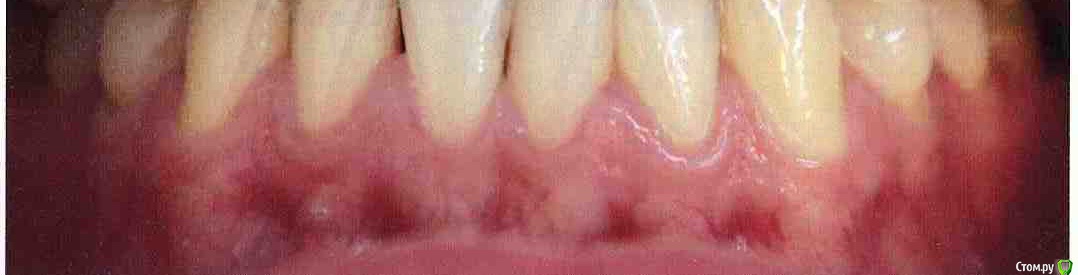

Olen' Опубликовано 16 февраля, 2016 Поделиться Опубликовано 16 февраля, 2016 (изменено) Дорогие доктора форума, Я, хотя и начитанный, в том числе этого форума, но всего лишь пациент. Итак, у меня, кроме других, есть проблема рецессии десны и хотя бы в работе с этой проблемой мне хотелось бы избежать беды, когда, особенно, в паре других вопросов стоматологических я в .... серьезно вляпалась и уже долго пытаюсь из этого вылезти.У меня есть хороший хирург (да простит он меня, что я вам пишу), которому я доверяю и лечить меня будет в любом случае он. Его мнение - закрытие рецессий.Но я также имею два других мнения, полученных в ходе моих попыток решить проблемы. Эти мнения совпадают: у меня мелкое преддверие полости рта и слизистые тяжи. Одно+второе=рецессии и клиновидные дефекты. Роль травматического прикуса в этих делах отрицается. Надо сказать, что говорят это врачи, у которых имеется опыт работы за рубежом, с зарубежными специалистами, изучение в оригинале работ зарубежных гуру по этой части. Их заключение: "вам нужна вестибулопластика, иначе через несколько лет вас обязательно ждет рецидив. Гуру пародонтологии так говорят, а кто говорит по-другому?" Скажите мне что-нибудь, пожалуйста, а? Я совершенно закономерно не понимаю, что мне делать, когда опытные и неглупые, в общем, врачи, ссылаясь на кучу источников, в том числе, иностранных, говорят мне то, что говорят. В данный момент ситуация с рецессиями чуть хуже, чем на фотографии. Но главное - преддверие, а что там с ним - и тут понятно. Вроде Изменено 16 февраля, 2016 пользователем Olen' Ссылка на комментарий